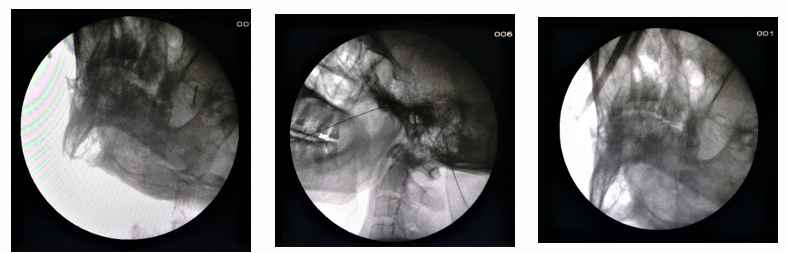

Radiofrequency Thermocoagulation (RFTC) is one of the most effective day-care procedure.It is done in operation theater under radiological guidance under local anesthesia and mild sedation. With 80 to 90% pain relief it has some drawbacks like, complain of numbness, and unusual sensation on the pain free zone.

"Radiofrequency ablation therapy"